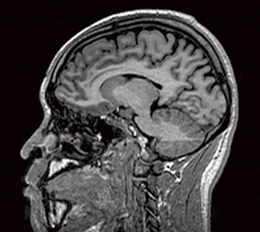

RSSGは,ステディステート型GrEシーケンスであり,高速3D撮像が可能です(図1)。RSSGは,早期アルツハイマー型認知症診断支援システム「VSRAD」(株式会社エーザイ)の推奨パルスシーケンスになっています。

図1 3D-RSSG頭部画像(TR/TE/FA=10.4/2.3/15°)